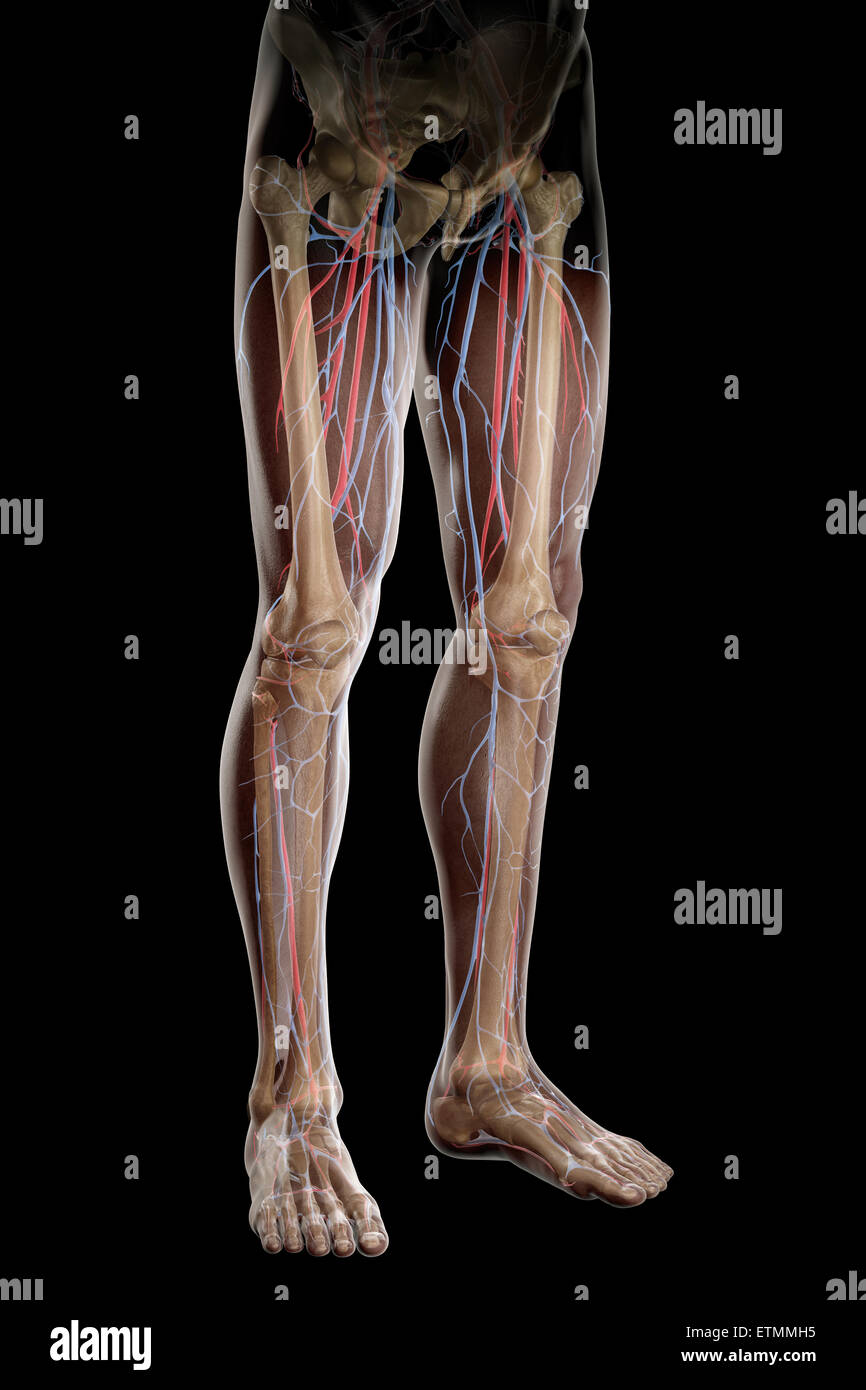

RF2KDED11–Arterielle Versorgung des vorderen und hinteren Beins über die Arteria poplitealis und ihre Zweige

RMETMN27–Darstellung der Blutversorgung und Skelett-Struktur der Unterschenkel, durch die Haut sichtbar.

RMETMNMF–Darstellung der Blutversorgung und Skelettsystem an den Unterschenkeln, durch die Haut sichtbar.

RMETMP9E–Darstellung der Blutversorgung und Skelett-Struktur der Unterschenkel, durch die Haut sichtbar.